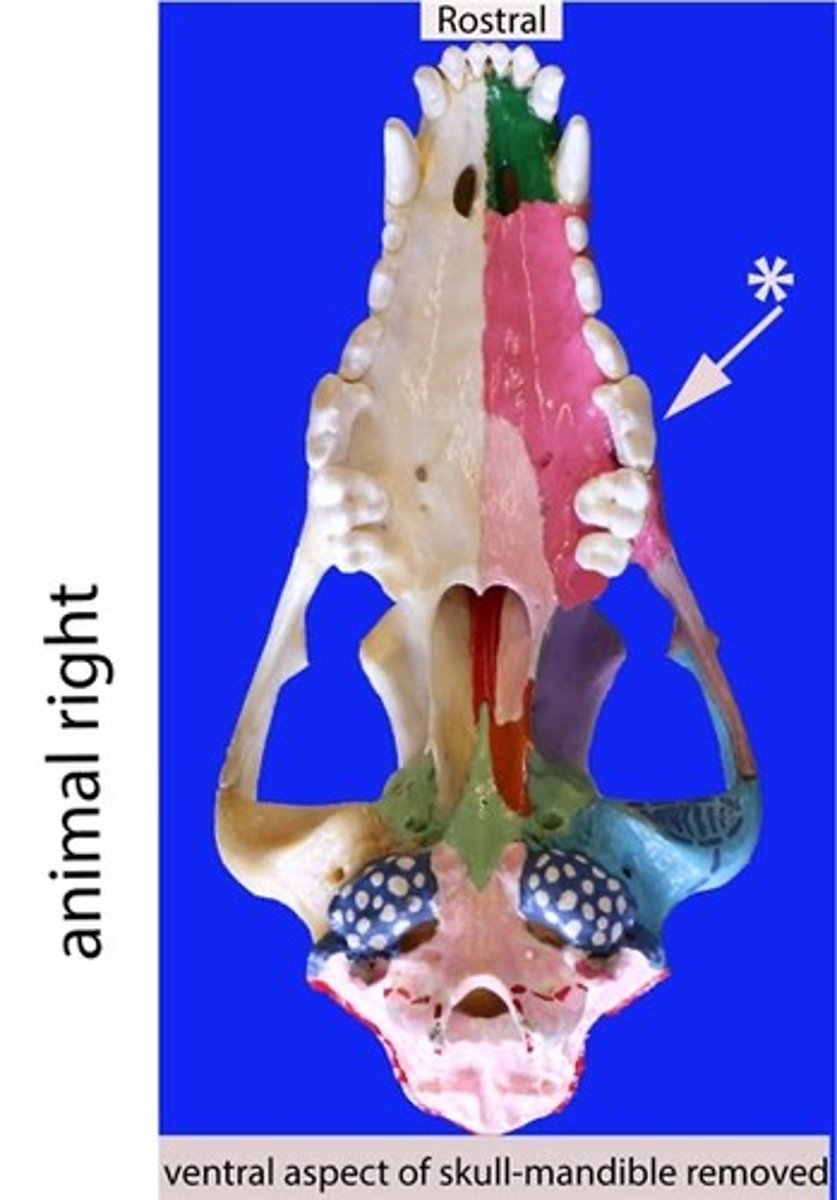

premolar

Identify the general type of tooth the arrow is pointing to

premolars

Identify the type of teeth shaded.

Premolar

Identify the type of tooth indicated by the arrow.